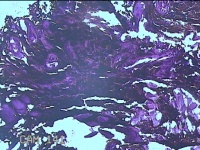

右手臂伸侧肿物

性别

女

年龄

27岁

临床诊断

纤维瘤病

一般病史

下腹部坠胀三天。

标本名称

大体所见

灰褐色肿物0.5x0.3x0.2cm一个,表面糜烂。

图1